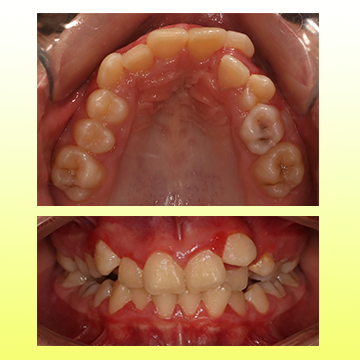

تو سن 8 سالگی با مشکل بیرون زدگی فک پایین و عقب بودن فک بالا مراجعه کرد. تحت درمان پیچ باز کننده فک بالا و فیس ماسک، مشکل فک کاملا درمان شد. بعد اون با ارتودنسی ثابت درمانش تکمیل شد.